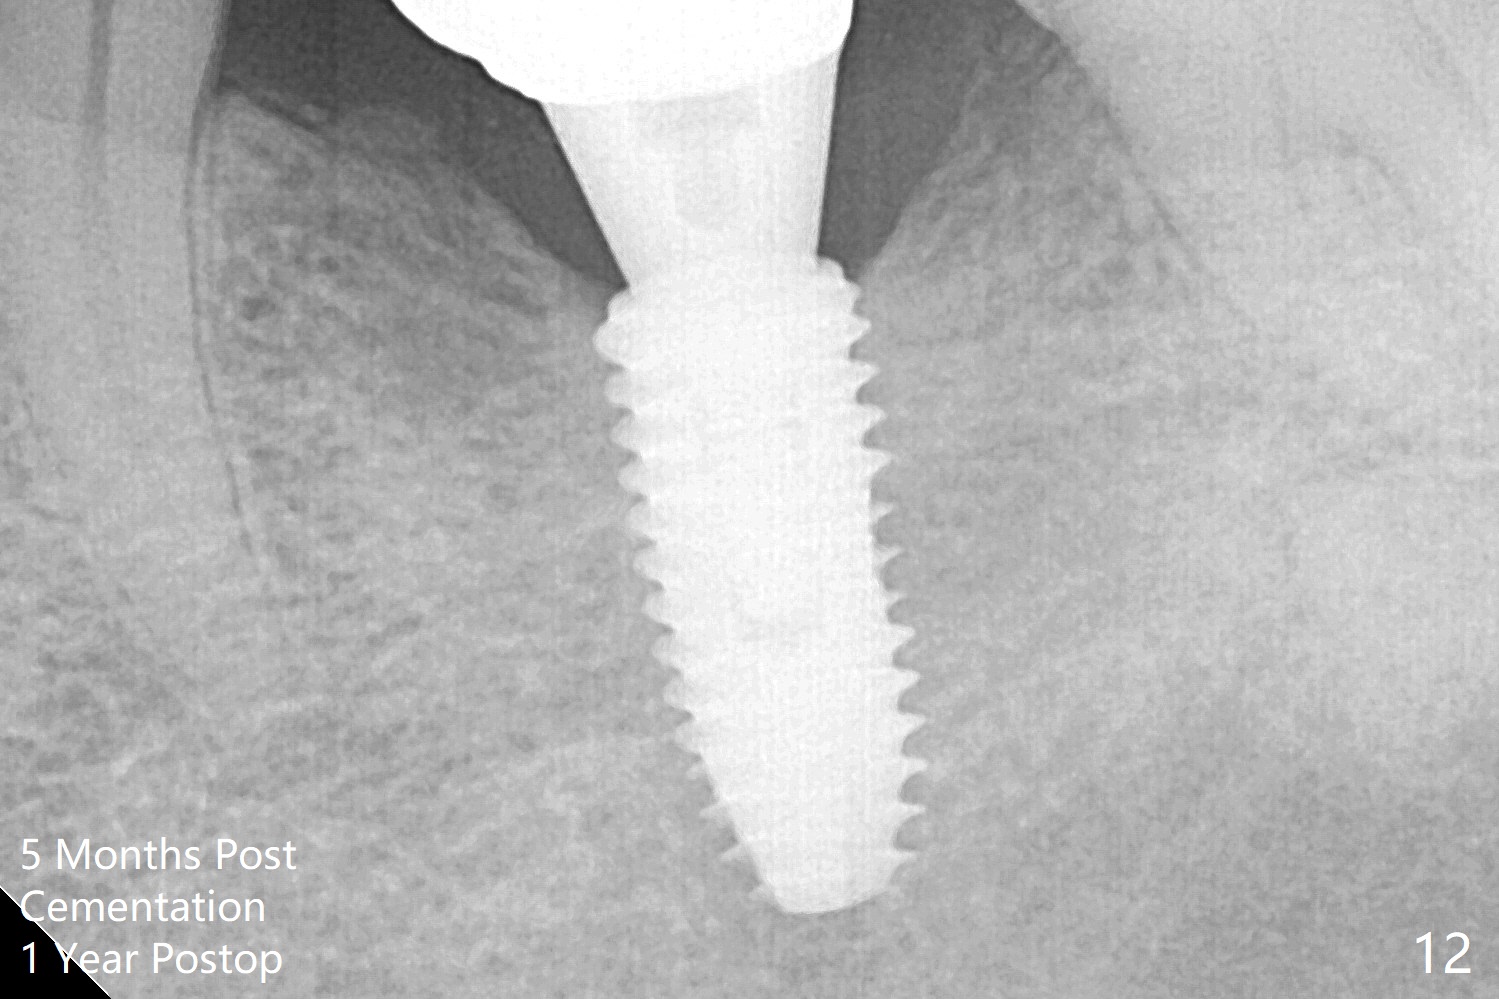

Note radiolucency around the implant (5x11.5 mm) before GBR (Fig.6). The bone density around the implant increases with distinct trabecular pattern consistent with stress 5 months post cementation (1 year postop, Fig.12).